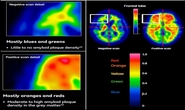

"알츠하이머 치매 시장의 개화"···듀켐바이오 치매 진단 방사성의약품 시장 의존도↑

듀켐바이오, 치매 진단제 표준 진단법으로 급부상